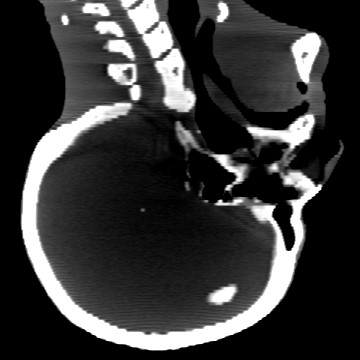

Cone-beam CT (CBCT) employs a flat-panel detector to achieve three-dimensional imaging with high spatial resolution. However, CBCT is susceptible to scatter during data acquisition, which introduces CT value bias and reduced tissue contrast in the reconstructed images, ultimately degrading diagnostic accuracy. To address this issue, we propose a deep learning-based scatter artifact correction method inspired by physical prior knowledge. Leveraging the fact that the observed point scatter probability density distribution exhibits rotational symmetry in the projection domain. The method uses Gaussian Radial Basis Functions (RBF) to model the point scatter function and embeds it into the Kolmogorov-Arnold Networks (KAN) layer, which provides efficient nonlinear mapping capabilities for learning high-dimensional scatter features. By incorporating the physical characteristics of the scattered photon distribution together with the complex function mapping capacity of KAN, the model improves its ability to accurately represent scatter. The effectiveness of the method is validated through both synthetic and real-scan experiments. Experimental results show that the model can effectively correct the scatter artifacts in the reconstructed images and is superior to the current methods in terms of quantitative metrics.